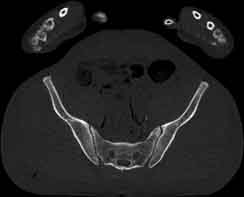

Visible Human male: Sectio transversalis 1809

CT

NMR

Pd                          / T2 \                         T1